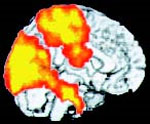

2. Etat de méditation

Voici l’image de l’état général pendant tout le YOGA NIDRA. Le centre visuel à l’arrière de la tête et le centre tactile (sens du toucher et de la direction) au sommet de la tête sont actifs et reliés au système limbique, impliquant une capacité accrue de visualisation et plus important un meilleur contact avec les émotions.

Certains professeurs révèlent aussi une activité distincte dans le centre de mémoire à long terme, ce qu’est en conformité des dires des pratiquants de méditation que des souvenirs très clairs peuvent subvenir pendant et après une méditation.

En regardant les images (1, 2 et 4) il faut imaginer que les parties lumineuses sont aussi à l’intérieur du cerveau et non juste à la surface du cortex. Sur l’image 3 par contre, c’est bien le cortex le siège de l’activité. Toutes les zones actives étaient pratiquement similaires, symétriques, dans les 2 hémisphères du cerveau.